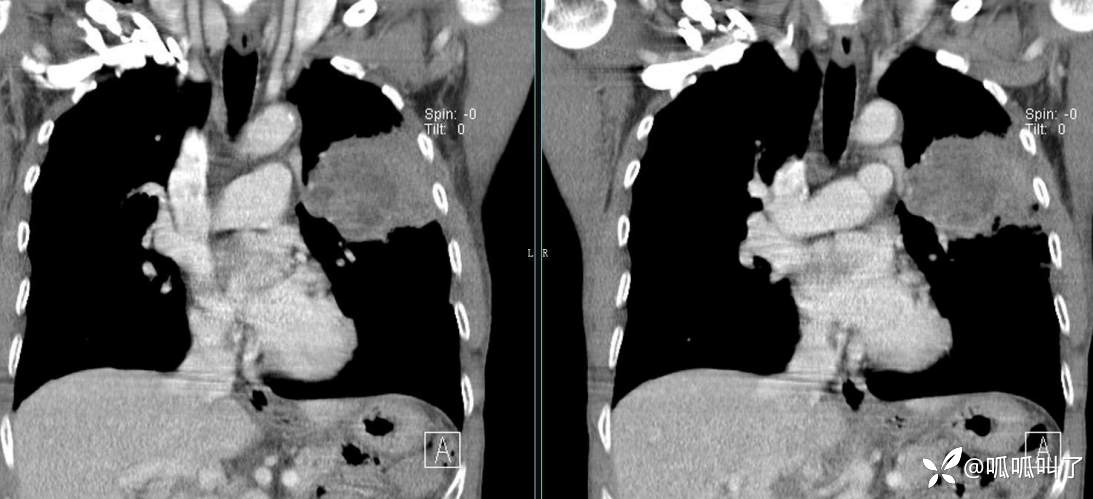

胸部CT平扫和增强: